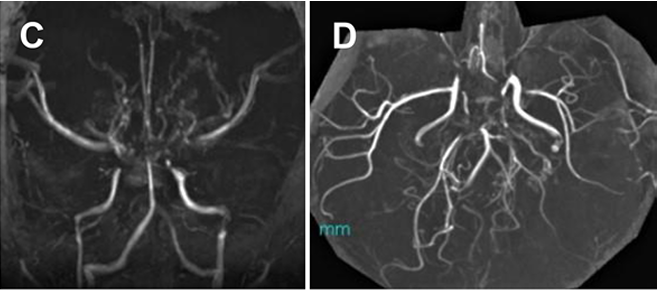

患者初次就診時進行的 FLAIR MRI,顯示 MMD 引起的雙側(cè)腦梗死